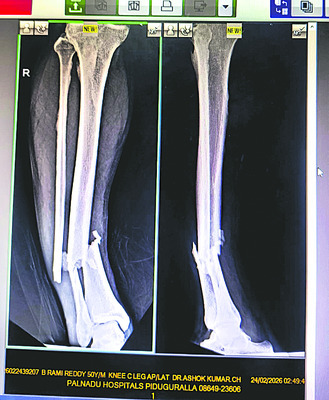

పిడుగురాళ్ల రూరల్/పిడుగురాళ్ల: అధికారం అండతో పచ్చమూకలు రెచ్చిపోతున్నాయి. వైఎస్సార్సీపీ నాయకులను టార్గెట్ చేసి.. విచ్చలవిడిగా హత్యాయత్నాలు, హత్యలకు పాల్పడుతూ రక్త దాహం తీర్చుకుంటున్నాయి. తాజాగా పల్నాడు జిల్లా జూలకల్లులో ఓ వైఎస్సార్సీపీ నాయకుడిపై టీడీపీ గూండాలు హత్యాయత్నం చేశారు. ఇనుప రాడ్లతో విచక్షణారహితంగా దాడి చేయడంతో.. ఆయన తీవ్రంగా గాయపడ్డారు. బాధితులు తెలిపిన వివరాలు.. జూలకల్లు గ్రామానికి చెందిన వైఎస్సార్సీపీ నాయకుడు బీరవల్లి రామిరెడ్డి వర్షం పడేలా ఉండటంతో సోమవారం అర్ధరాత్రి పొలానికి వెళ్లాడు. మొక్కజొన్న కండెలపై పట్టాలు కప్పి ఇంటికి బయల్దేరాడు. అప్పటికే ఆయనపై నిఘా పెట్టిన టీడీపీ గూండాలు ఇనుముక్కల సామేలు, షేక్ దాదాసాహెబ్, చల్లా మోజెస్, సింహాద్రి మరికొందరు ఒక్కసారిగా రామిరెడ్డిపై విరుచుకుపడ్డారు. ఇనుప రాడ్లు, కర్రలతో విచక్షణారహితంగా దాడి చేశారు. రామిరెడ్డి స్పృహ కోల్పోవడంతో.. వారంతా వెళ్లిపోయారు. అనంతరం కొద్దిసేపటికి అటుగా వెళ్లిన కొందరు.. రామిరెడ్డిని చూసి కుటుంబసభ్యులకు, బంధువులకు సమాచారమిచ్చారు. కుటుంబసభ్యులు వెంటనే ఘటనాస్థలానికి చేరుకొని రామిరెడ్డిని పిడుగురాళ్లలోని ఓ ప్రైవేటు ఆస్పత్రికి తరలించారు. వైద్య పరీక్షలు చేసిన డాక్టర్లు.. రామిరెడ్డి కాళ్లు, ఎడం చేయి విరిగినట్లు తెలిపారు. దీంతో కుటుంబసభ్యులు పట్టణ పోలీస్స్టేషన్లో ఫిర్యాదు చేశారు. కాగా, బీరవల్లి రామిరెడ్డిని మాజీ ఎమ్మెల్యే, వైఎస్సార్సీపీ నేత కాసు మహేష్రెడ్డి పరామర్శించారు. గురజాల నియోజకవర్గంలో గూండా రాజ్యం నడుస్తోందని మండిపడ్డారు. జూలకల్లులో ఇప్పటికే ఆరుగురిపై టీడీపీ గూండాలు దాడి చేశారని చెప్పారు. ఇంకా మూడేళ్లు మాత్రమే ఉందని.. దాడులు చేసే వారు, చేయించే వాళ్లు ఇంతకింతా అనుభవించే రోజులు వస్తాయన్నారు. చట్టపరంగా శిక్షలు పడే రోజులు దగ్గరలోనే ఉన్నాయని హెచ్చరించారు.